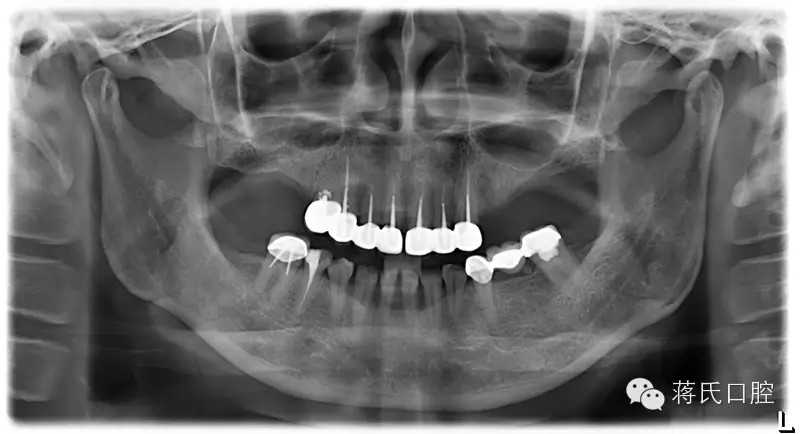

患者情況 女 49歲 ,三類(lèi)骨,右上區(qū)骨高度6毫米, 寬度8毫米。左上區(qū)骨最低點(diǎn)1毫米,寬度3毫米

種植前X線(xiàn),左側(cè)外提升右側(cè)內(nèi)提升